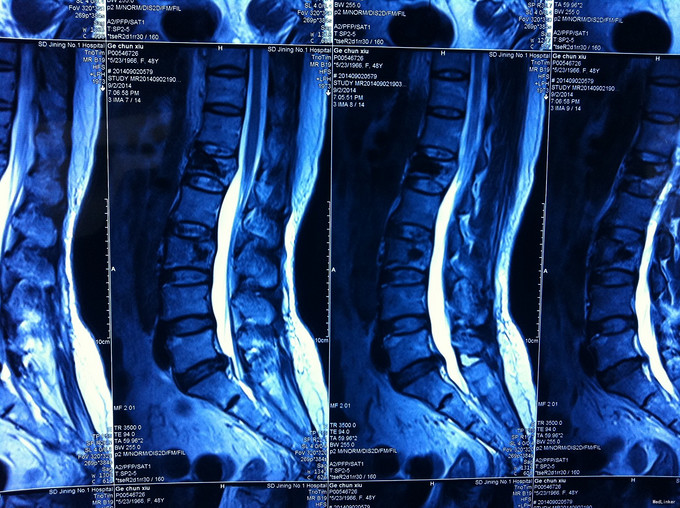

外伤致腰部疼痛活动受限2天入院 患者2天前被车撞伤致腰部疼痛、活动受限,不伴双下肢放射性疼痛、无力,无鞍区麻木、大小便费力,双下肢活动可。双下肢活动可。

专科查体无下肢神经损伤表现:腰部叩痛,腰部活动受限,双下肢感觉无异常,双下肢肌力4-5级,双侧膝腱反射++,跟腱反射+,双侧巴氏征阴性, X-ray:腰1椎体骨折,累及前中柱,腰3椎体骨折。CT:腰1、3椎体骨折,累及中柱。MR:腰1、3骨折,新鲜骨折。影像学检查提示腰1椎体骨折较重。

诊断:腰椎骨折 腰1、3椎体 处理:1、完善相关辅助检查,明确诊断,有无手术指证; 2、完善手术评估,有无手术禁忌,手术风险及并发症; 3、在全麻下行腰1椎体后路撑开复位内固定术,腰3椎体压缩较轻,可卧床保守治疗。